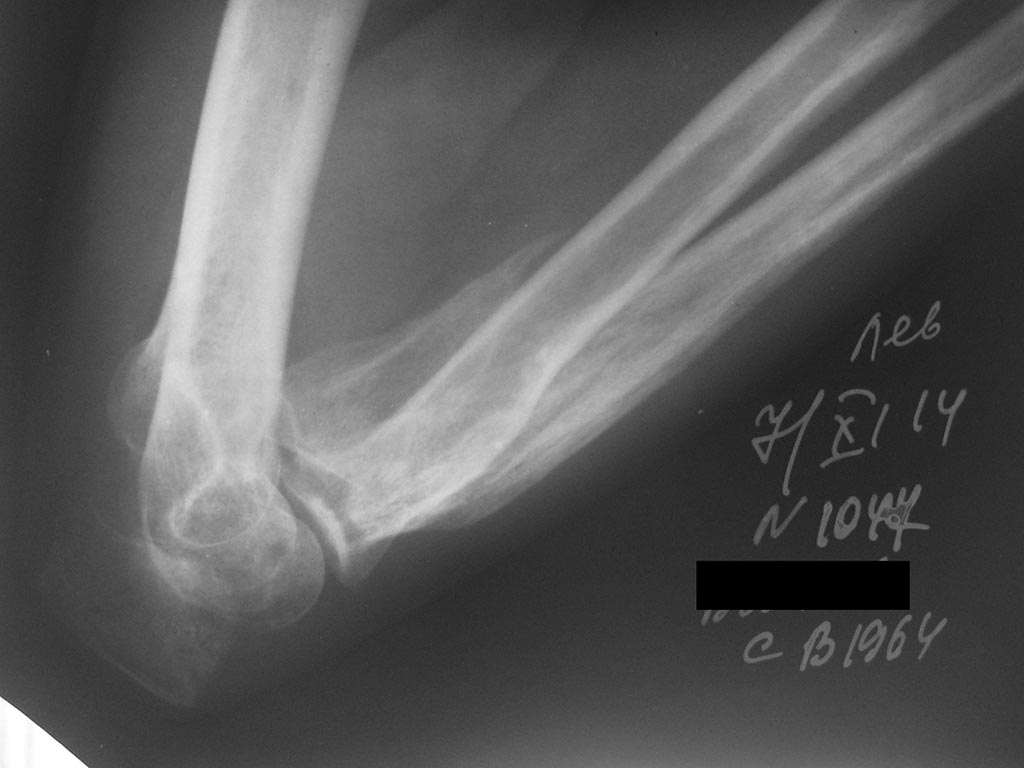

Лечения не было. Сейчас - контрактура и резко выраженный болевой синдром, в т.ч. вследствие давления trohlea humeri изнутри на кожу.

Судя по последнему снимку - дело в тюрьме?

Качество первых двух снимков очень плохое. А на двух последних, по моему, перелом локтевого отростка. Если так, то просто остеосинтез

Локтевого отростка и передней стенки локтевой кости

6 месяцев для такой травмы очень большой срок. Предполагаю, будут трудности в ходе операции. По хорошему надо фиксировать и локтевой и венечный отросток с участков локтевой кости. Венечный через передний доступ по Henry, 2 винтами, локтевой отросток по Веберу, постаравшись ввести спицы бикортикально.